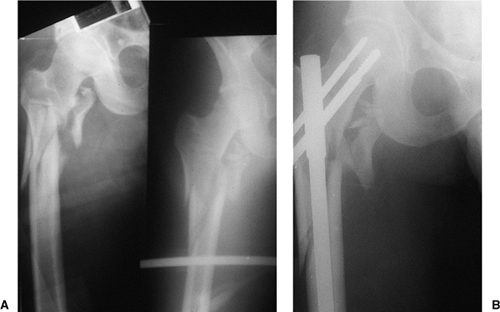

malfunction while jumping. On impact, he had a closed, displaced,

proximal, femur fracture (Fig. 20.46). The

patient underwent reamed, static, reconstruction nailing. His fracture

united at 3 months, and he returned to his work without restrictions.

This fracture pattern probably represents the ideal indication for a

reconstruction nail; that is, it was a subtrochanteric fracture with

loss of medial cortical stability and with fracture of the lesser

trochanter (Russell–Taylor IB). The fracture did not extend into the

piriformis fossa.

Figure 20.46. A,B. Subtrochanteric fracture caused from parachuting accident. Stabilization with Russell-Taylor reconstruction nail, static mode.